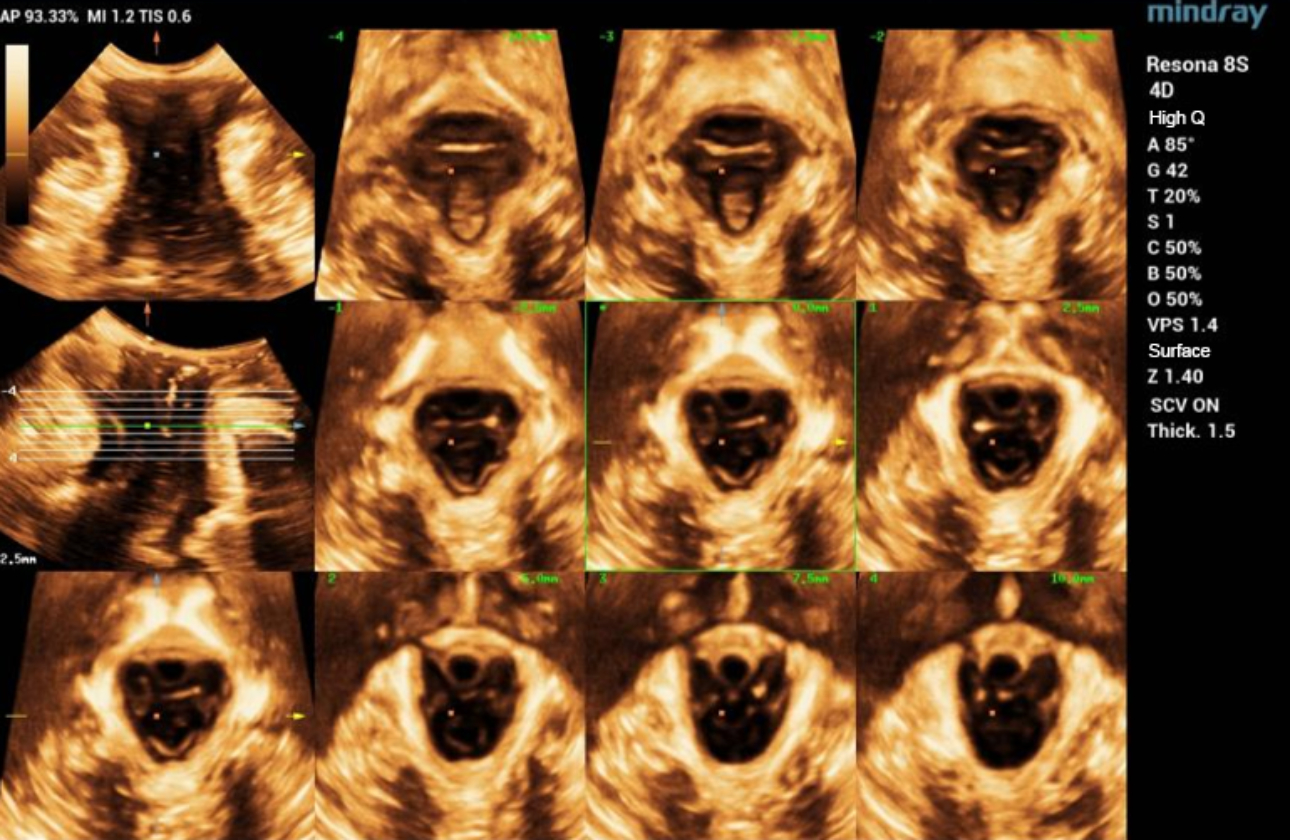

?? ?? ????? parasagittal view??? ???/?? 2D ???, 3D/4D ?? ??, Ipage+?? ?? ?? ?? ???? ?????.

?? 39??? 30???(G1P1)?? ??? Negative-pressure vacuum extraction? left perineotomy? ?????, ???? ???? 3.387kg?????. Pelvic floor ???? ?? 42? ? ???????.

- 2D ?? : ???? ??? ?? ?? ???? interruption? ?? ???? ??? ?? ??? ??.

- Levator hiatus? ?????? ?? ????? ?? ??.

- Ipage+ : ? ? ??? slice?? ?? ?? ?? levator avulsion? ?? ??, levator trauma ??? ??? ? ? ??.